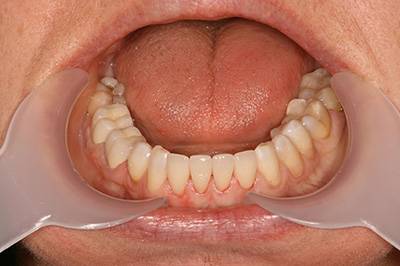

3. eset

4 implantátumra rögzített stéggel stabilizált "Overdenture" megoldás. Költséghatékony módszer fogsorok rögzítésére. Nagyfokú stabilitás érhető el redukált felületeken. Ebben az esetben jól látható, hogy a szájpadlást nem fedi be a kivehető fogsor, az ízlelés is megmarad, mégis javul a rágási képesség és a fogsorok mozgásmentesen rögzülnek.